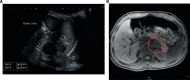

Case presentation: Here, we report a pure androgen-secreting adrenocortical tumor in a 2.5-year-old boy presenting with penile enlargement, pubic hair, frequent erections, and rapid linear growth. We confirmed the diagnosis through laboratory tests, medical imaging, and histology. Furthermore, genetic testing detected a pathogenic germline variant in the TP53 gene, molecularly confirming underlying Li-Fraumeni syndrome.

Discussion: Only 15 well-documented cases of pure androgen-secreting adrenocortical tumors have been reported so far. No clinical or imaging signs were identified to differentiate adenomas from carcinomas, and no other cases of Li-Fraumeni syndrome were diagnosed in the four patients that underwent genetic testing. However, diagnosing Li-Fraumeni syndrome is important as it implies a need for intensive tumor surveillance and avoidance of ionizing radiation.